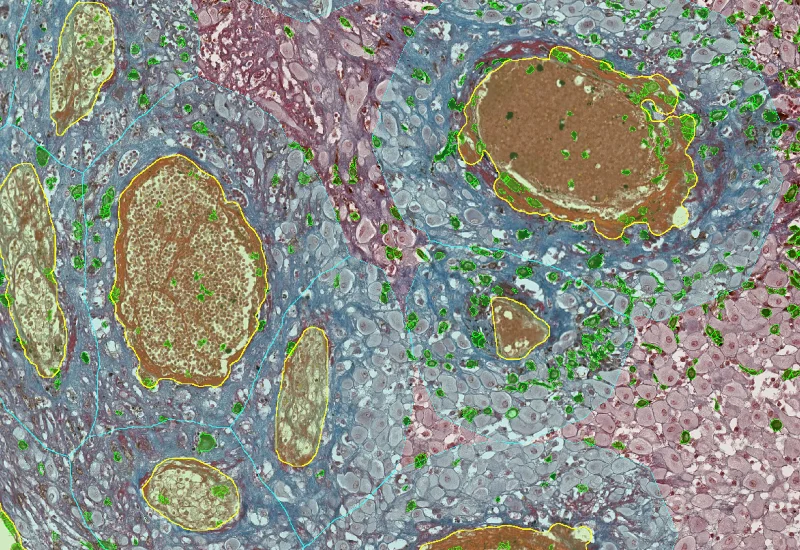

Evaluating the Distance of Tumor Cells from Blood Vessels

CD31, blood vessels, diameter

Detect blood vessels based on appropriate stains (e.g. CD31), measure vessel and lumen areas, and export vessel number, density, and areas of vessels, endothelium, and lumina.

Segment tissue into tumor and stroma/healthy areas, detect CD31+ vessels, and quantify vessel number, area, density, and connectivity with configurable wall closing and distance linking.